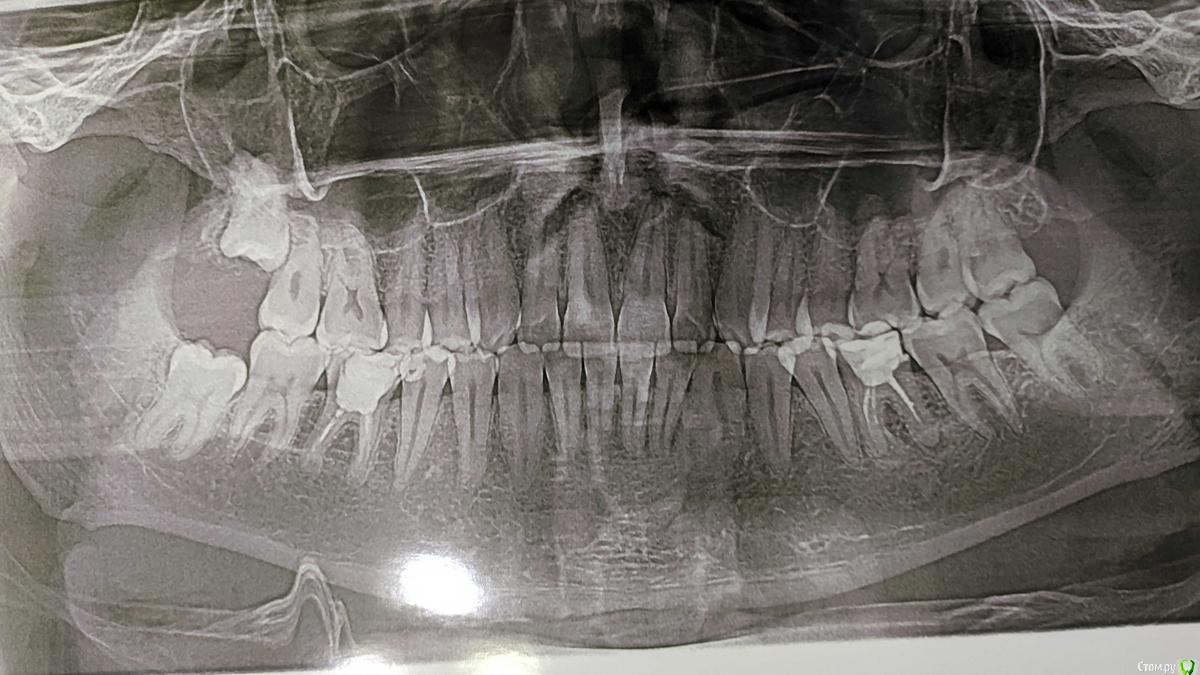

Иван Пятов Опубликовано 5 февраля, 2020 Поделиться Опубликовано 5 февраля, 2020 Добрый день! Мне 30 лет, зубы мудрости никак не беспокоят, но мне говорят что нужно удалять ретинированные зубы мудрости (до недавнего времени даже не знал что они у меня есть), так говорит терапевт и ортопед. Но хирурги при этом начинают говорить что зубы сидят очень глубоко и сверху могут быть проблемы с гайморовыми пазухами (какие проблемы я правда не понял), а снизу соответственно с нервом и пол лица может остаться онемевшим, и говорят что на момент осмотра показаний к удалению нет с их слов))). Вопрос нужно ли мне их вообще удалять, они как я понял уже выросли и дальше могут вообще не вырасти и какие последствия если их не удалить. Потому-что как понимаю риск при удалении в моем случае тоже большой получить проблемы. 1 Ссылка на комментарий

Irouil Опубликовано 5 февраля, 2020 Поделиться Опубликовано 5 февраля, 2020 А я бы удалил все, кроме, может быть, правого верхнего, включая оба левых, что прорезались. Ну и замечу, что под большим вопросом нижние шестерки Ссылка на комментарий

Irouil Опубликовано 5 февраля, 2020 Поделиться Опубликовано 5 февраля, 2020 А левые то за что?Бьюсь о заклад, что ретромолярно у 3.8 лежит хлюпающий капюшон, ожидающий абсцессика с рисками провала в крылочелюстное. Надо, конечно, во рту посмотреть, чтобы убедиться. Ссылка на комментарий

Irouil Опубликовано 6 февраля, 2020 Поделиться Опубликовано 6 февраля, 2020 А зачем удалять левые 8ки, они прорезались и стоят в прикусе.Бьюсь о заклад, что ретромолярно у 3.8 лежит хлюпающий капюшон, ожидающий абсцессика с рисками провала в крылочелюстное. Надо, конечно, во рту посмотреть, чтобы убедиться.С правой же стороны никаких проблем тоже нет, хирург смотрел, сказал на момент осмотра пару недель назад показаний к удалению нет. А при удалении описал разные варианты осложнений. Тут вопрос насколько действительно сложна такая процедура и каков риск осложнений после удаления?Правая нижняя восьмёрка лежит эмалью под тонким слоем десны. Вероятность того, что в этом месте сформируется пролежень и зуб частично прорежется - высокая, а в таком состоянии он станет воротами для входа бактерий в Ваш организм. Однако, если его удалить сейчас, то ведение раны элементарное - бросаются два шва и все заживает. Если же он успеет немного прорезаться - зашить рану просто так уже не получится, а значит либо рана будет заживать дольше и хуже, либо придётся проводить пластику дефекта мягкими тканями, что а) делают не все клиницисты б) усложняет реабилитацию (больше отеки и боли в первые несколько суток) На данный момент, судя по снимкам, риски каких-то серьёзных осложнений удаления правого нижнего зуба невелики. 1 Ссылка на комментарий

Марья Моревна Опубликовано 6 февраля, 2020 Поделиться Опубликовано 6 февраля, 2020 Кариес 47 может быть бессимптомный,а затем и пульпит.Но удалять 48 должен квалифицированный хирург,наподобие тех,что выше отвечали.Ради этого можно и подъехать куда-то. А может, на форуме посоветуют доктора поближе. Ссылка на комментарий